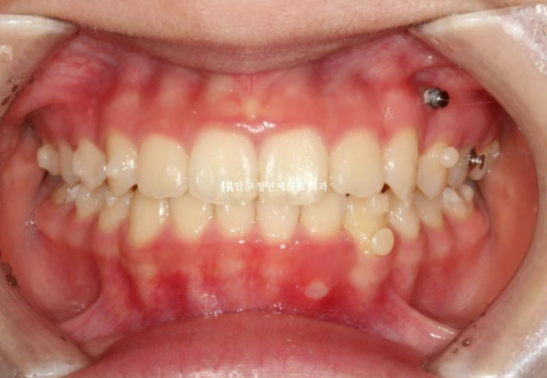

그리고 추가장치를 4달간 더 낀 후의 모습입니다.

중심선은 잘 맞아졌습니다.

24.07

교합도 좋습니다.

23.08~24.07

무엇보다 한쪽의 3급 어금니 교합관계는 1급이 되었습니다.